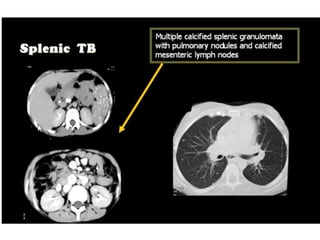

This document discusses the spleen and causes of splenomegaly (enlarged spleen). It begins by thanking radiologists for their assistance. Simple cyst criteria are outlined. Splenogonadal fusion and sarcoidosis are mentioned. The main causes of splenomegaly are then listed, including infections, portal hypertension, hemolytic anemias, hematological malignancies, infiltrative disorders, collagen vascular disorders, and congestive cardiac failure.